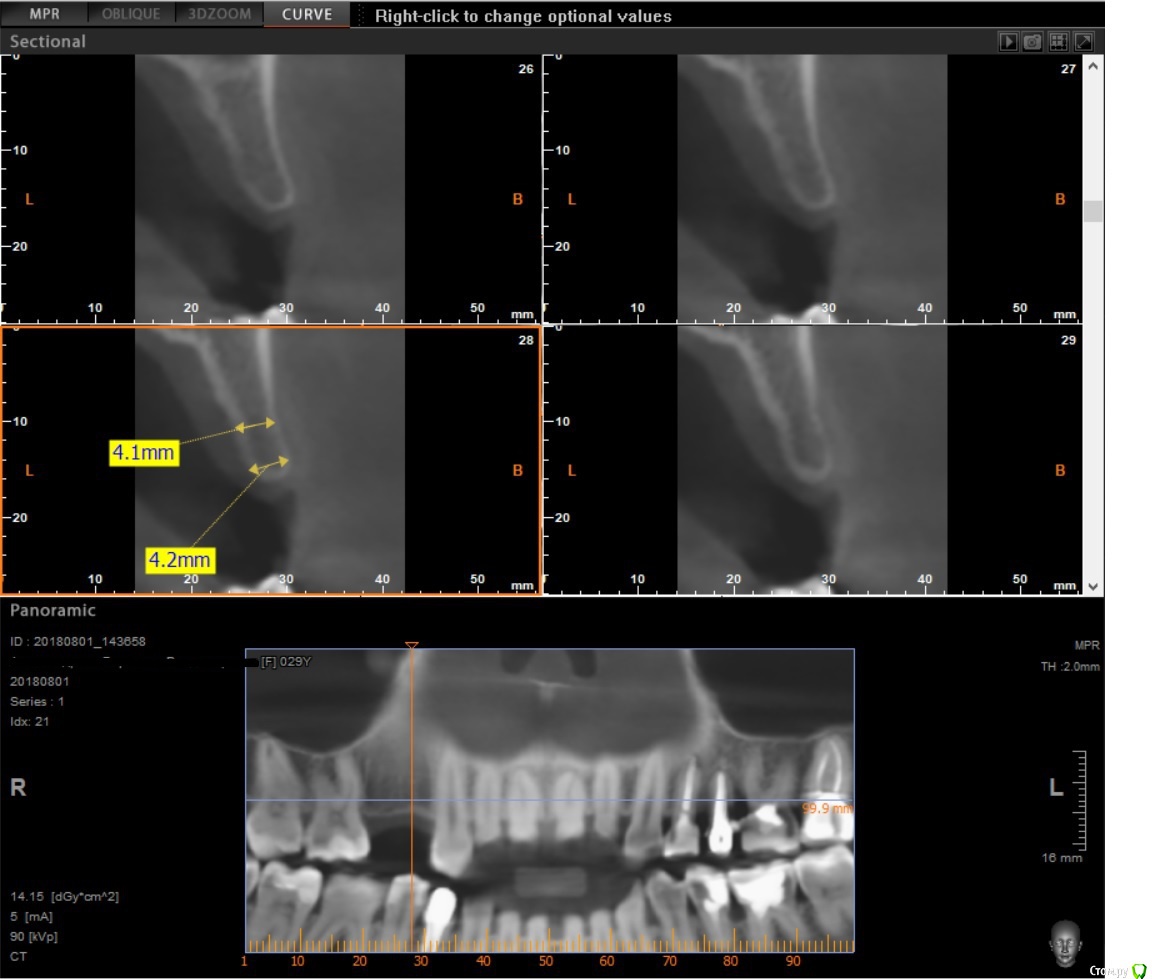

x4ex Опубликовано 29 августа, 2018 Поделиться Опубликовано 29 августа, 2018 (изменено) По всей видимости между экваторами 13 и 16 там около 10мм. Исходя из этого, я бы пошёл по 3 варианту с одним имплантатом нормальной ширины в области 15, только без немедленной нагрузки. Изменено 29 августа, 2018 пользователем x4ex Ссылка на комментарий

Тимур86 Опубликовано 29 августа, 2018 Поделиться Опубликовано 29 августа, 2018 ощущение что Вы чуть недомерили кость Ссылка на комментарий

Foxtrot Опубликовано 29 августа, 2018 Автор Поделиться Опубликовано 29 августа, 2018 ощущение что Вы чуть недомерили кость прошу прощения. Без очков не вижу Ссылка на комментарий